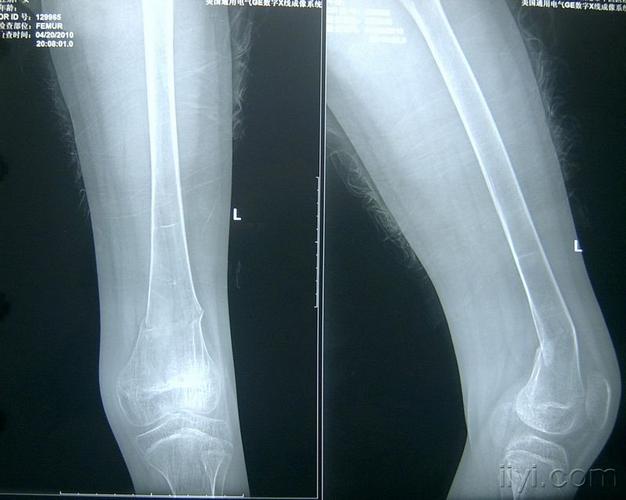

左股骨远端青枝骨折